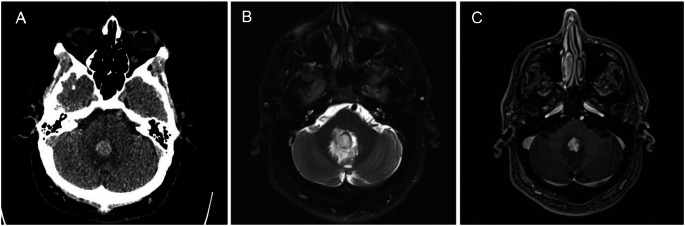

Results: 222 patients met study inclusion criteria, with a median age of 67 and 43.2% female sex. 188 patients (84.7%) had a history of hypertension, while 14 (6.3%) had a urine drug screen positive for cocaine or amphetamines during their hospital admission. The majority of hemorrhages were centered in the basal ganglia or internal capsules (116, 52.3%). Brain MRI was obtained for 120 (54.1%) of cases at a median interval of 0.97 days following the initial head CT, and of these studies, 85 (70.8%) included postcontrast imaging. Only 1 MRI study (0.8%) identified a culprit lesion adjacent to a cerebellar hematoma, which was later found to represent a pilocytic astrocytoma. 33.8% of patients overall met the modified Hong Kong Rule. Of the 77 MRIs performed in patients not meeting the modified Hong Kong Rule, 0 revealed a culprit lesion.